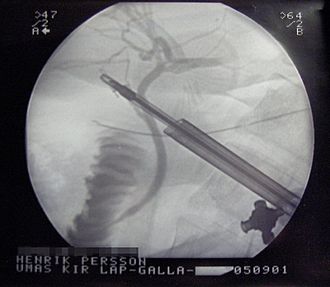

Najvažniji je oblik liječenja. Kolecistektomija označava operativno uklanjanje žučnog mjehura. Hitna kolecistektomija (unutar 72 sata) indicirana je u svakog akutnog kolecistitisa ako je dijagnoza jasna. Time se spjrečavaju komplikacije i skraćuje boravak u bolnici. Najčešće se izvodi laparoskopska kolecistektomija.